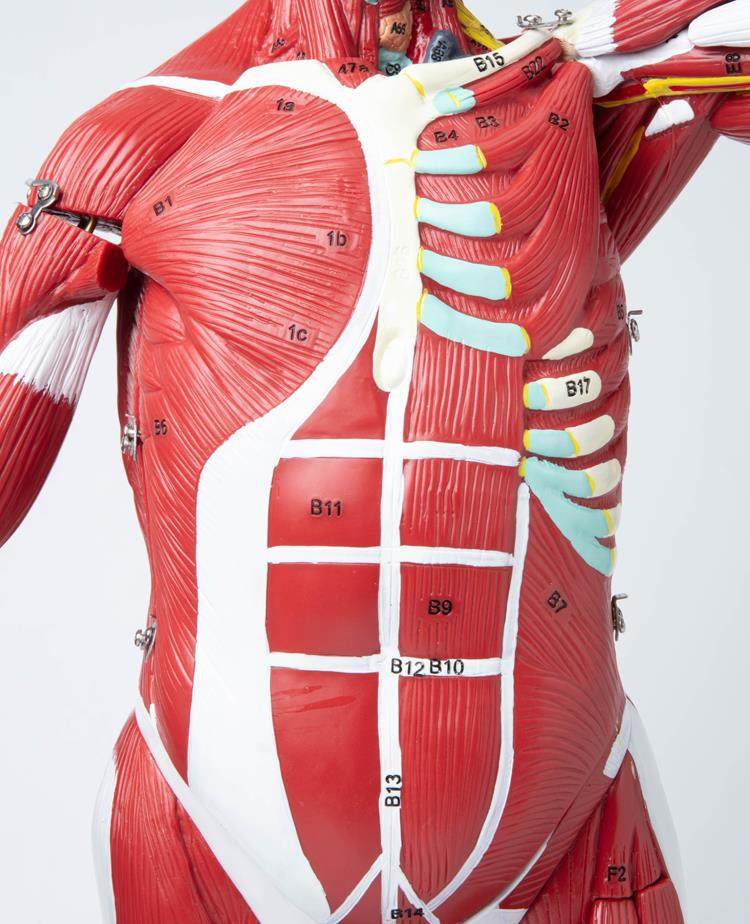

Human Body Muscle Internal Organ Disassembly Anatomy Structure Model Tissue Exercise Artificial Medical Teaching Aids

| Color Classification | 85 Human Muscle Internal Organs Removable Organ,50cm Muscle Model |